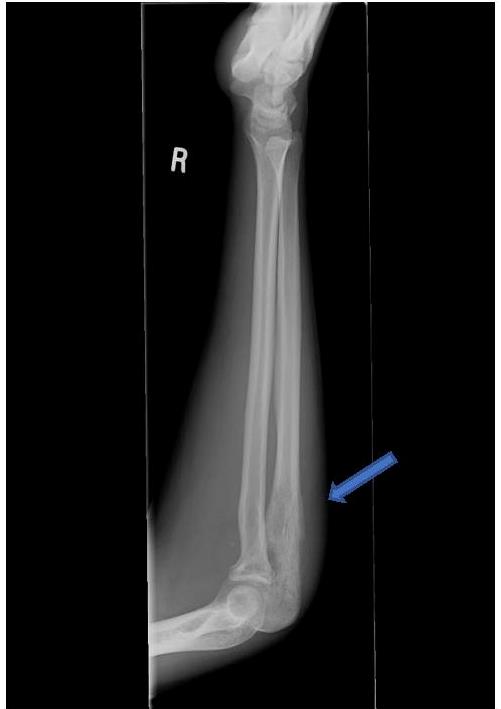

![]() |

Image G : Lateral radiograph right radius and ulna – periosteal elevation (Codman triangle) adjacent to an area of permeative bone destruction in proximal ulna . |